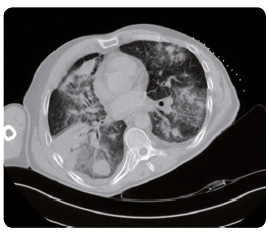

Pacient (ročník 1961) přichází s prvními příznaky nemoci do naší ambulance koncem května 2014 pro hmotnostní úbytek 7 kg za tři měsíce a s pocitem dušnosti provázeným suchým pokašláváním. Muž je jen příležitostným kuřákem, bez komorbidit, pracuje jako operátor na velíně. Na skiagramu hrudníku (obr. 1) nález hodnotíme jako nejspíše pokročilý tumor horního laloku pravé plíce. Na CT (computed tomography, počítačová tomografie) hrudníku a horní části břicha ze dne 22. května 2014 (obr. 2) nacházíme v S1/3 pravé plíce spikulovité ložisko o velikosti 43 mm × 39 mm × 47 mm – nejspíše primární bronchogenní karcinom. V plicích jsou přítomny difuzně oboustranně mnohočetné metastázy v rozsahu 5–30 mm, vpravo zhruba 19 mm, vlevo 30 mm, parahilózně a v dolních lalocích karcinomatózní

lymfangoitida. Fluidothorax vpravo je v šíři 27 mm, vlevo 4 mm. Dokumentovány jsou zvětšené lymfatické uzliny v okolí trachey a v aortopulmonálním okénku i v hilech bilaterálně. V oblasti jater se nacházejí hypodenzní ložiska o velikosti až 19 mm v největším průměru. Současně je popsáno ložisko metastázy ve štítné žláze, které ověřujeme ultrasonograficky a následně punkčně.